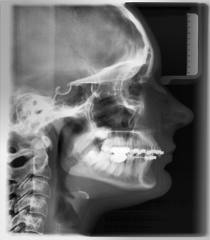

Ukoliko se odlučite da kod nas nastavite sa terapijom, dijagnostika mora da se dopuni uzimanjem otisaka za studijske modele, fotografisanjem lica i zuba i još jednim rendgenskim snimkom-profilnim snimkom glave. Na osnovu otisaka, dobijaju se gipsani studijski modeli-replika vaših zubnih lukova. Na tim modelima ortodont vrši precizna merenja i tako dolazi do tačne dijagnoze i mogućnosti za terapijsku proceduru.

Na osnovu sprovedene anamneze, kliničkog i funkcionalnog ispitivanja, analize rendgenskih snimaka, studijskih modela i fotografija, ortodont dobija sve relevantne podatke o ortodontskom problemu jednog pacijenta. Sve te podatke on sklapa u jedinstvenu dijagnozu i  odlučuje koji terapijski postupak je najbolji za datog pacijenta.

profilni telerendgen snimak